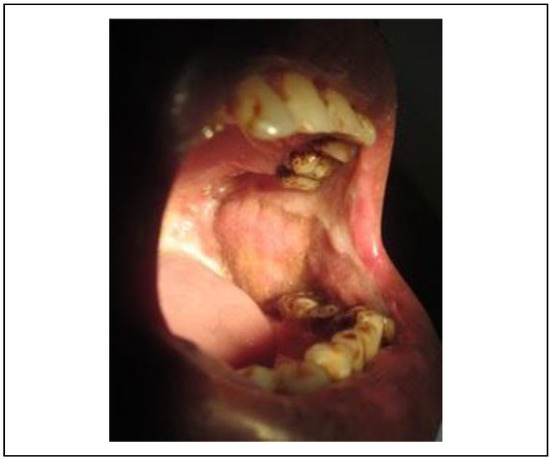

Numerous studies have reported the use of the NLF for the closure of fibrotomy defect and the defects of the upper lip, tongue, and gingival sulcus. The versatility of this flap is attributed to its reliable vascularity derived from numerous vessels in the vicinity. It is advocated because of the ease of elevation, proximity to the defect, minimal swallowing and speech difficulties, and a relatively cosmetic result as the scar is formed in a natural crease. The BFP which has also been used for the coverage of the defect after fibrotic band excision is simple due to easy access[9]; however, the tissue of this flap may be inadequate for the complete coverage of the defect which is the biggest disadvantage of this flap (Figure 3). The gradual recurrence of trismus was observed due to islands of mild secondary fibrosis if aggressive physiotherapy is not performed (Figure 4).

Figure 3. BFP inability to provide volume and cover entire defect. BFP indicates buccal fat pad.